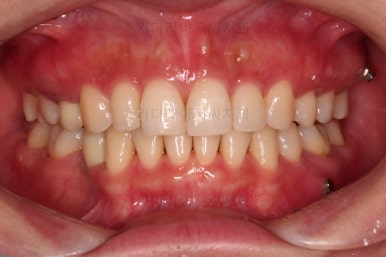

초진 시 입안의 모습인데요.

왜 그런지 비밀이 풀리는 것 같죠?

윗니는 한 쪽이 치아 2개가 결손이면서 유치가 하나 남아있고요.

아랫니는 한 쪽은 1개, 반대편은 2개 치아가 결손이었습니다.

도합 5개의 치아가 결손이었는데요.

결손 위치의 갯수가 위아래 좌우 다 달라서 중앙선이 맞을래야 맞을 수가 없는 상황이었죠.

결손치아 주위 치아들은 쓰러지고 비틀어져 있어서 장기적으로 좋지 못한 상황이었고요.

좀 더 디테일하게 윗니 작은 앞니 1개가 왜소치아라서 치아 크기도 맞지 않은 상황이었습니다.